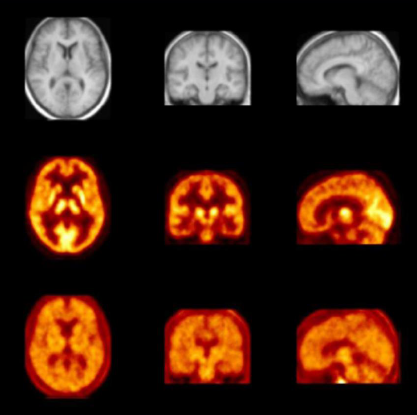

ÓÃЯ´øÕýµç×Ó·¢Éä·ÅÉäÐÔÍ¬Î»ËØµÄPETÒ©Îï·Ö×Ó¾ÙÐÐÉúÎïÂþÑÜÑо¿¿ÉÒÔ²âÊÔл¯Ñ§ÊµÌåÊÇ·ñµÖ´ï×ã¹»Á¿µÄÄ¿µÄ×éÖ¯¸ôÊÒ£¨ÀýÈç´óÄÔ£©Ò©Àí»îÐÔ¡£¡£¡£¡£¡£¾ºÕùÑо¿£¬£¬£¬£¬£¬Ê¹Ó÷ÅÉäÐÔÅäÌåÓëÖÎÁÆÐ԰еãÁ¬Ïµ³ä·ÖÌØÒìÐÔ£¬£¬£¬£¬£¬Äܹ»Ö±½ÓÆÀ¹ÀÒ©ÎïѪ½¬Å¨¶ÈÓëÄ¿µÄÕ¼ÓÃÂÊÖ®¼äµÄ¹ØÏµ¡£¡£¡£¡£¡£Á¿Éí¶¨ÖÆµÄ·ÅÉäÐÔʾ×Ù¼Á¿ÉÓÃÓÚÕÉÁ¿ÉúÎïÀú³ÌµÄÏà±ÈÕÕÂÊ£¬£¬£¬£¬£¬¶ø×éÖ¯±ê¼ÇÌØÒìÐԵķÅÉäÐÔÅäÌåÔ¤ÆÚ»áËæÖ®¸Ä±äÖÎÁÆ¿ÉÒÔÌá¹©ÌØ¶¨µÄҩЧÐÅÏ¢£¬£¬£¬£¬£¬Õë¶Ô¼²²¡Àú³ÌµÄ¶´²ì£¬£¬£¬£¬£¬ÐÂÖÎÁưбêµÄÓÐÓÃÐÔ£¬£¬£¬£¬£¬°Ð/·Ç°ÐÆ÷¹ÙÏ໥×÷Ó㬣¬£¬£¬£¬×÷ÓûúÖÆ£¬£¬£¬£¬£¬ÉúÎïÂþÑܵȵȡ£¡£¡£¡£¡£MIµÄÆæÒìÌØÕ÷ΪҩÎïÑз¢Ö°Ô±ÌṩÁËÒ»¸öÔçÆÚ½â¾ö¼Æ»®£¬£¬£¬£¬£¬ÓÃÓÚÆÀ¹ÀÐÂÒ©ÎïÑз¢µÄÒªº¦ÔÔò£ºÒ©Îï°ÐµãµÄ¶¨Î»£¬£¬£¬£¬£¬Óë¸ÐÐËȤµÄ°ÐµãÁ¬ÏµÒÔ¼°ËùÐèµÄÒ©ÀíѧÆÀ¹À¡£¡£¡£¡£¡£½«MI½â¾ö¼Æ»®ÄÉÈëеÄÒ©ÎïÑз¢ÍýÏ룬£¬£¬£¬£¬½«ÔÊÐíÒ©Î﹫˾ÔÚÒ©Î↑·¢Àú³ÌµÄÔçÆÚ¿ìËÙÆÀ¹ÀЧ¹û²¢×÷³öÖ÷Òª¾öÒé¡£¡£¡£¡£¡£

¹ØÓÚÖÐÊàÉñ¾ÏµÍ³ºòѡҩÎ£¬£¬£¬£¬Î¢Á¿¸øÒ©¶ÔÑо¿ÑªÄÔÆÁÕÏ´©Í¸¡¢ÊÜÌåÁ¬Ïµ»ò¼ÁÁ¿Óë°ÐÆ÷¹ÙµÄ¹ØÏµÌØÊâÓÐÒâÒå¡£¡£¡£¡£¡£±ðµÄ£¬£¬£¬£¬£¬Ð³´úлµÄµÚÒ»¸öÖ¤¾Ý¿ÉÒÔ»ñµÃ¡£¡£¡£¡£¡£Î¢Á¿¸øÒ©¾ßÓÐÏ൱´óµÄ±¾Ç®ºÍʱ¼äÓÅÊÆ£¬£¬£¬£¬£¬ÓÐÖúÓÚ½µµÍÖÐÊàÉñ¾ÏµÍ³»¯ºÏÎ↑·¢ÖеÄÏûºÄÂÊ¡£¡£¡£¡£¡£

·ÅÉäÐÔʾ×Ù¼Á±ê¼ÇµÄPETÑо¿¿ÉÒÔ¶¨Á¿ÆÀ¹ÀÒ©ÎïµÄÒ©´ú¶¯Á¦Ñ§ºÍ´úл¡£¡£¡£¡£¡£Á¬ÏµÐÐΪѧµÈҩЧÊý¾Ý£¬£¬£¬£¬£¬Ò©´ú¶¯Á¦Ñ§PETÑо¿¿ÉÒÔ×ÊÖúÑо¿Ö°Ô±½¨Éè¼ÁÁ¿-ÁÆÐ§¹ØÏµºÍ¼ÁÁ¿È·¶¨¡£¡£¡£¡£¡£Í¬Ê±Ê¹ÓÃPET»¹¿ÉÒÔ×·×Ùµ½Ò©ÎïÔÚ°Ð×éÖ¯µÄÇøÓòÂþÑÜ¡£¡£¡£¡£¡£

¡÷×ó£ºÒ©ÎïÔÚСÊó¸¹Ç»µÄ¶¯Ì¬ÂþÑÜ£»£»£»£»ÓÒ£ºÒ©ÎïÔÚÄÔµÄÇøÓòÂþÑÜ